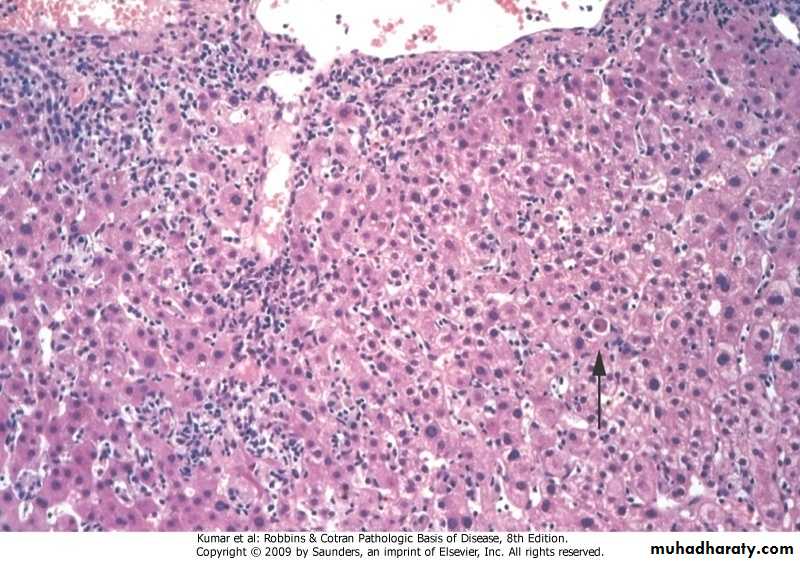

Acute viral hepatitis, Lobular inflammation

Ballooning degeneration